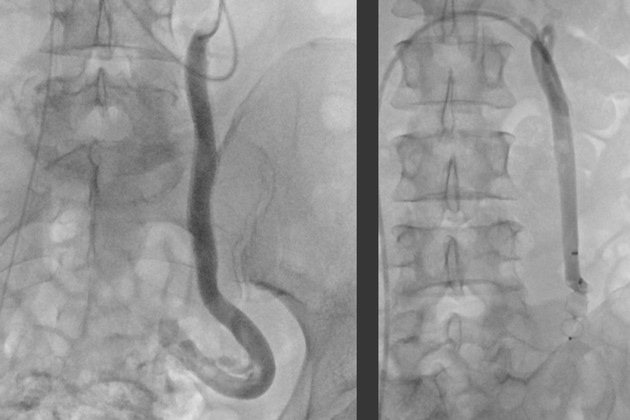

Bei der Embolisation wird ein dünner Katheter über die Leiste (selten auch über einen Zugang am Arm oder Hals) in die Vene eingeführt. Unter Röntgenkontrolle und Kontrastmittelgabe wird dieser Katheter zu den erweiterten Beckenvenen vorgeschoben. Die betroffenen Venen werden nun gezielt von innen verödet und anschließend mit kleinen Spiralen oder speziellen „Stöpseln“ über den Katheter verschlossen. Dadurch wird der krankhafte Rückfluss des Blutes unterbrochen. Der venöse Abfluss erfolgt danach problemlose über gesunde Umgehungswege.